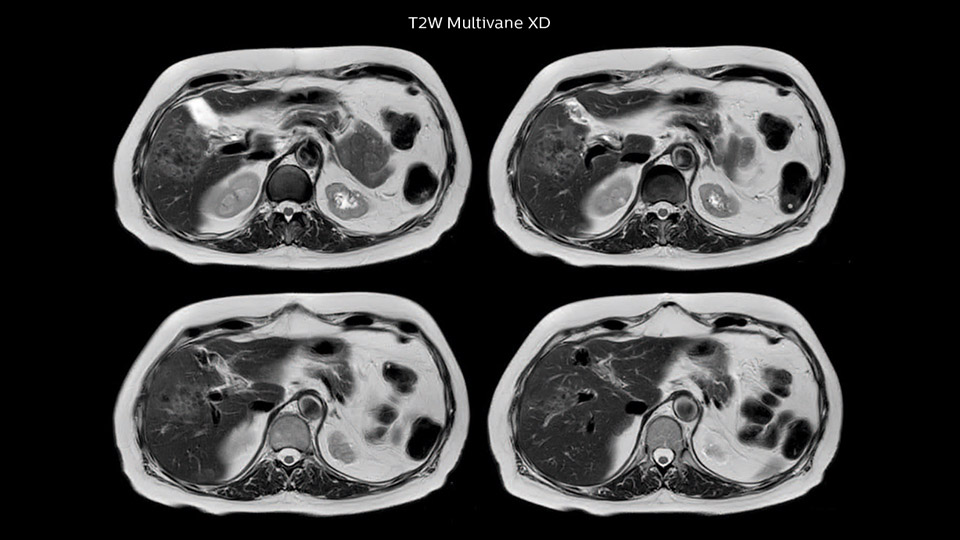

“We acquire one transversal high resolution T2-weighted sequence with 3 mm slice thickness, for example for pancreas or liver lesions. Then we also add a T2 fat suppressed MultiVane XD SPIR sequence. We perform these two routinely in our liver imaging. We use high dS SENSE factors to significantly shorten scan times to 2-4 minutes, which can improve our protocol; it’s a very robust scan.”

Comparison of liver MRI with and without MultiVane XD motion correction

In this example the image quality of the MultiVane XD images is evidently better than in the images without MultiVane XD. Ingenia 1.5T with dS Torso coil solution.